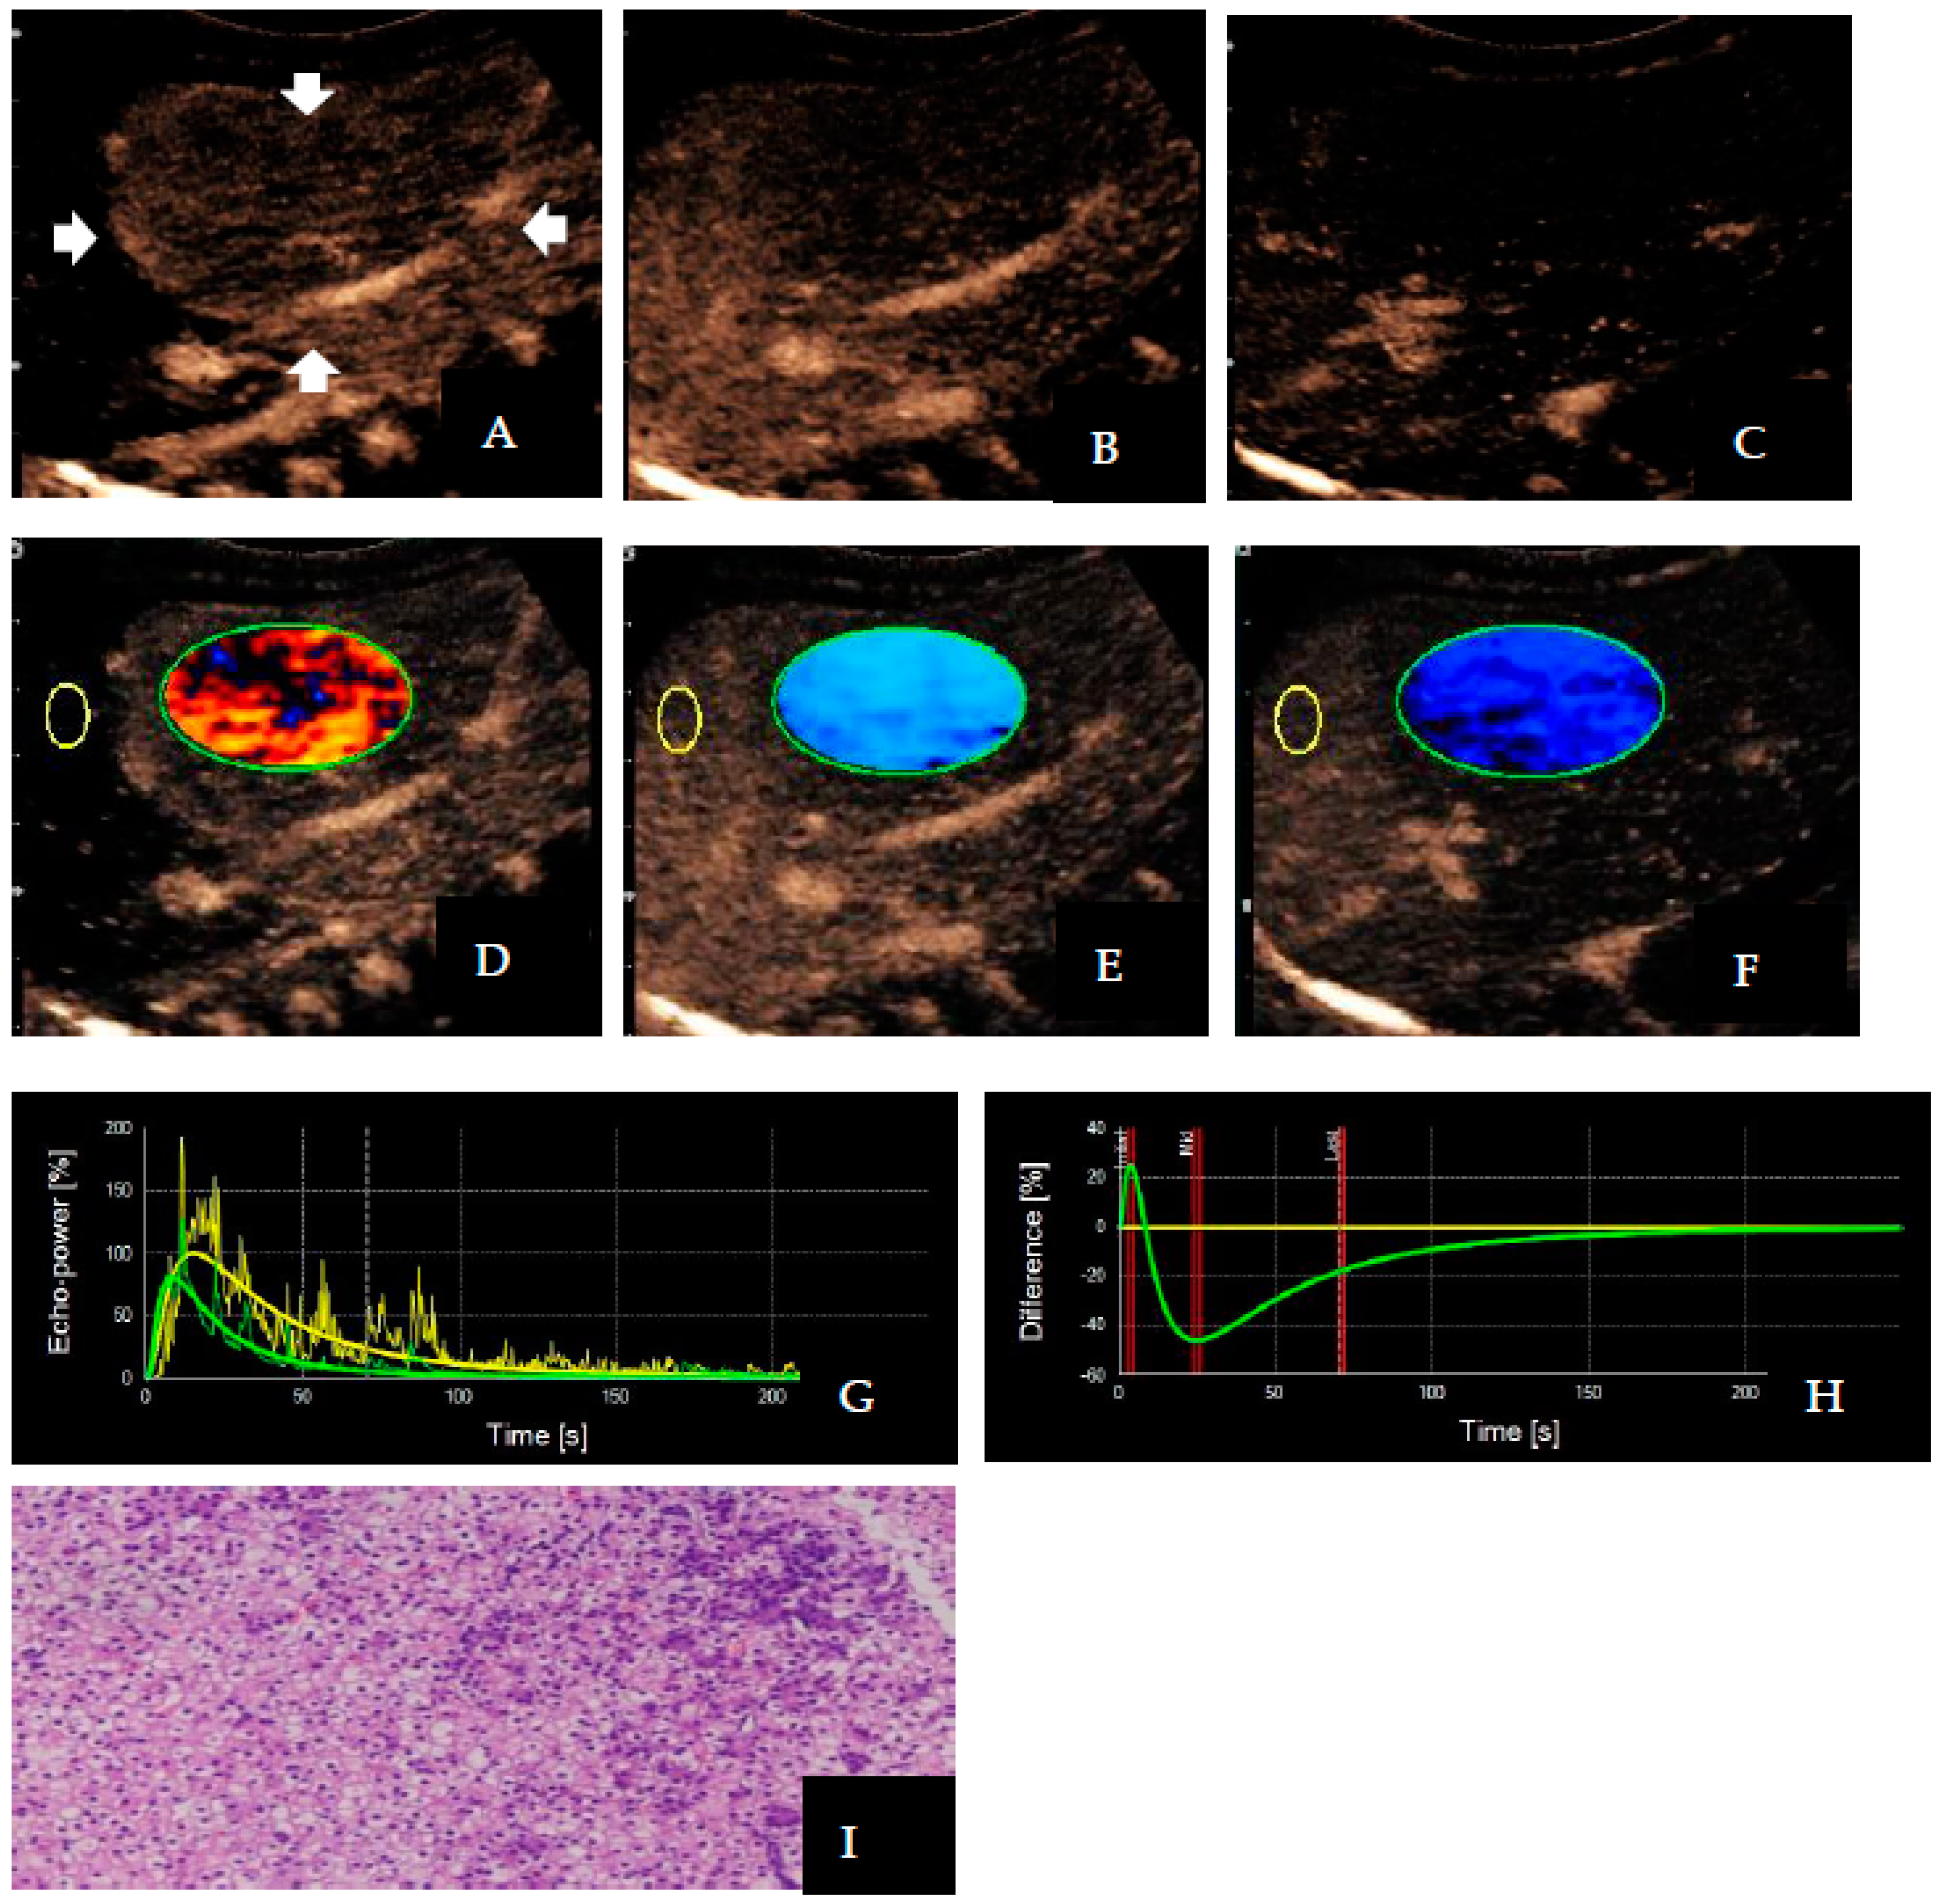

Figure 3. Images of a 4-month-old boy with confirmed hepatoblastoma. The lesion is located in the right lobe of the liver (arrows). Contrast-enhanced ultrasound enhancement images showed (A) hyper-enhancement (5 s), (B) hypo-enhancement (25 s), and sustained (C) hypo-enhancement (70 s); as a result, dynamic vascular pattern parametric images appeared (D) red, (E) blue, and (F) blue, respectively (Type I). The effect of the portal washout on the parametric images was evident, despite the subtle effect of the washout in the portal phase on contrast-enhanced ultrasound. The time–intensity curve showed (G) rapidly increasing and rapidly decreasing waves, and the dynamic vascular pattern showed positive and negative biphasic waves (H); the puncture specimen microscopically showed (I) epithelioid tumor cells, with focal nuclei of large, dark staining in a nested cluster, diagnosed as hepatoblastoma (HE × 40). In this case, the yellow circle represents the region of interest in the reference area and the green circle represents the region of interest in the target lesion area; the green curve indicates the enhancement of the lesion, the yellow curve indicates the enhancement of the adjacent hepatic parenchyma, and the yellow curve flattens out in the dynamic vascular pattern curve. The three red lines in (H) represent three different time points where the contrast agent enters.

The distribution of TIC and DVP differed significantly between benign and malignant liver tumors (Table 3 and Table 4). In 88.57% (31/35) of cases involving malignant liver lesions, hyper-enhancement with rapid washout patterns was observed. The TIC showed rapidly increasing and rapidly decreasing waves, and the DVP showed positive and negative biphasic waves (Figure 3). However, 94.44% (17/18) of benign liver lesions showed hyper-enhancement with slow washout patterns, TIC showed rapidly increasing and slowly decreasing waves, and DVP showed positive wave (Figure 4). Only one malignant tumor with sacrococcygeal yolk cystoma liver metastasis showed hypo-enhancement with rapid washout patterns. The DVP displayed a negative wave in this case. For DVP parametric images, the percentages of Types I, II, and III were 60.38% (32/53), 37.73% (20/53), and 1.89% (1/53), respectively. Among them, Type I accounted for 88.57% (31/35) of the malignant liver tumors, and Type II accounted for 94.44% (17/18) of the benign liver tumors.